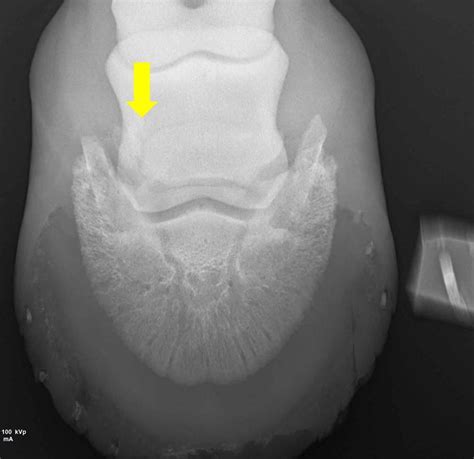

Because a scaphoid bone fracture does not always appear on an initial X-ray, doctors often rely on clinical examination and follow-up imaging. If a doctor suspects a fracture despite clear X-rays, they may immobilize the wrist and order repeat imaging in one to two weeks. During this time, the fracture line often becomes more visible as the bone begins to resorb.

X-ray Imaging Primary scan to identify major breaks or displacement.

MRI or CT Scan Used for occult fractures that are hidden on standard X-rays.